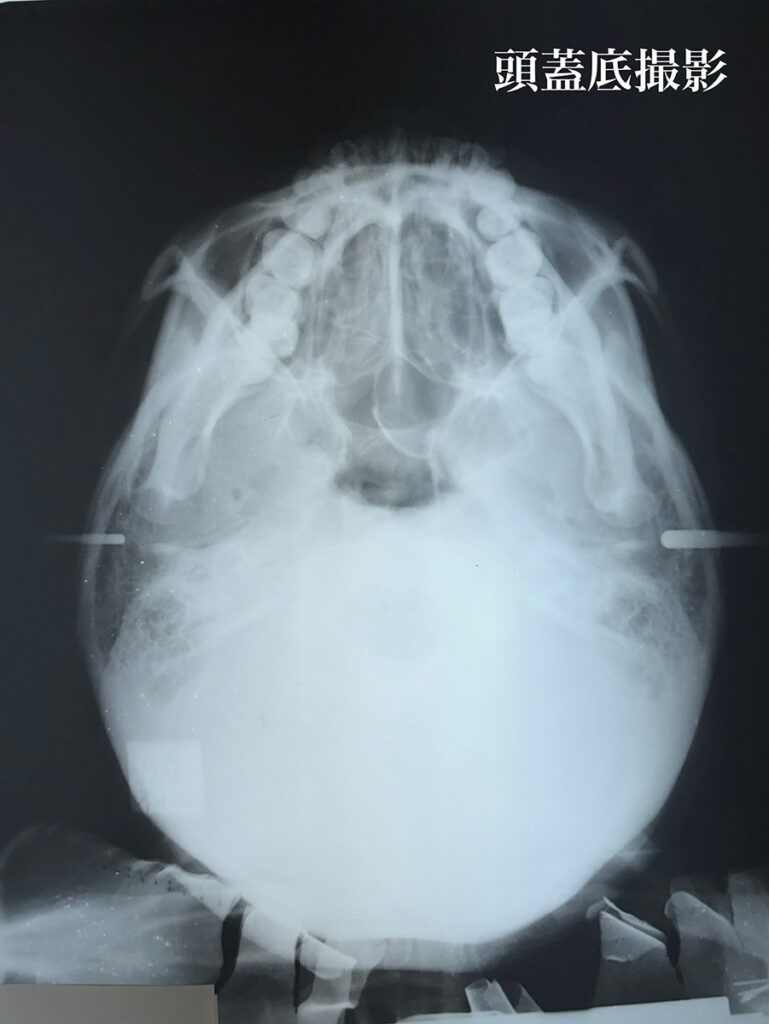

レントゲン所見においては、矯正歯科治療においてセファロ写真分析は欠かせません。

しかし、それだけでは情報量としては不足だと考えています。

私はレントゲンメーカーの協力によって特注の機器を製作していただき臨床に活用しております。頭蓋骨の3軸方向からの分析し、骨の変形とともに、頭蓋骨と下顎骨との位置的関係について精査し、正しい咬み合わせでの歯科矯正治療を確実に行います。